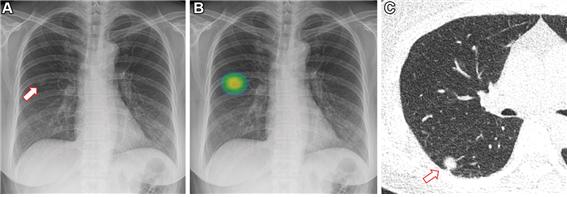

인공지능 사용군의 경우 루닛 인사이트를 활용해 인공지능이 병변을 컬러맵으로 표시해주면 영상의학과 전문의가 이 결과를 참고해 최종 판독했고, 인공지능 비사용군의 경우 영상의학과 전문의가 인공지능 기반 CAD 활용 없이 흉부 X선 영상을 해석했다.

그 결과, 인공지능 사용군의 폐 결절 검출률은 0.59%(5238명 중 31명)로, 비사용군의 0.25%(5238명 중 13명)에 비해 약 2.4배 유의미하게 높았다.